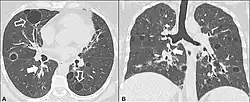

CT scan of lymphocytic interstitial pneumonia, with pulmonary cysts. | |